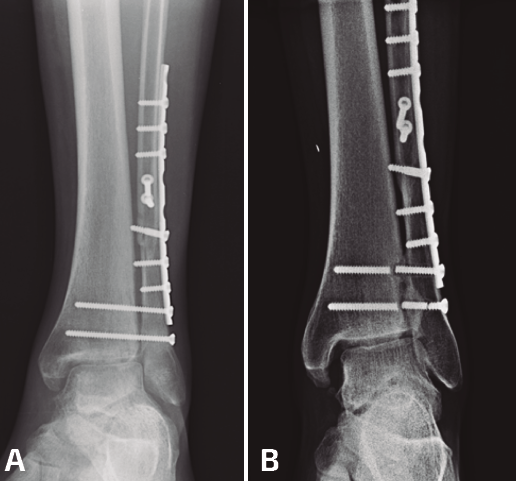

- Diástasis tras retirada (Figura 3). Complicación posiblemente insuficientemente registrada, aproximadamente en un 15% de los casos en los que se retira el tornillo(14). Las causas pueden ser una malreducción inicial (no diagnosticada por sobrecompresión de la sindesmosis) o, más raramente, por un aflojamiento o una rotura precoces que no hayan permitido la cicatrización de la sindesmosis.

Figura 3. A: fractura suprasindesmal del peroné sintetizada con placa tercio de caña y 2 tornillos transindesmales; B: mismo caso a los 3 años de seguimiento con rotura de tornillos y apertura de la sindesmosis con cambios degenerativos tibioastragalinos.